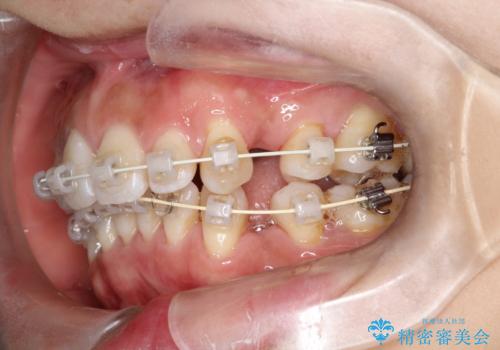

- 矯正装置

- 審美装置

矯正を開始する前から歯肉退縮があり、悪化しないように注意しながら矯正治療を行いました。